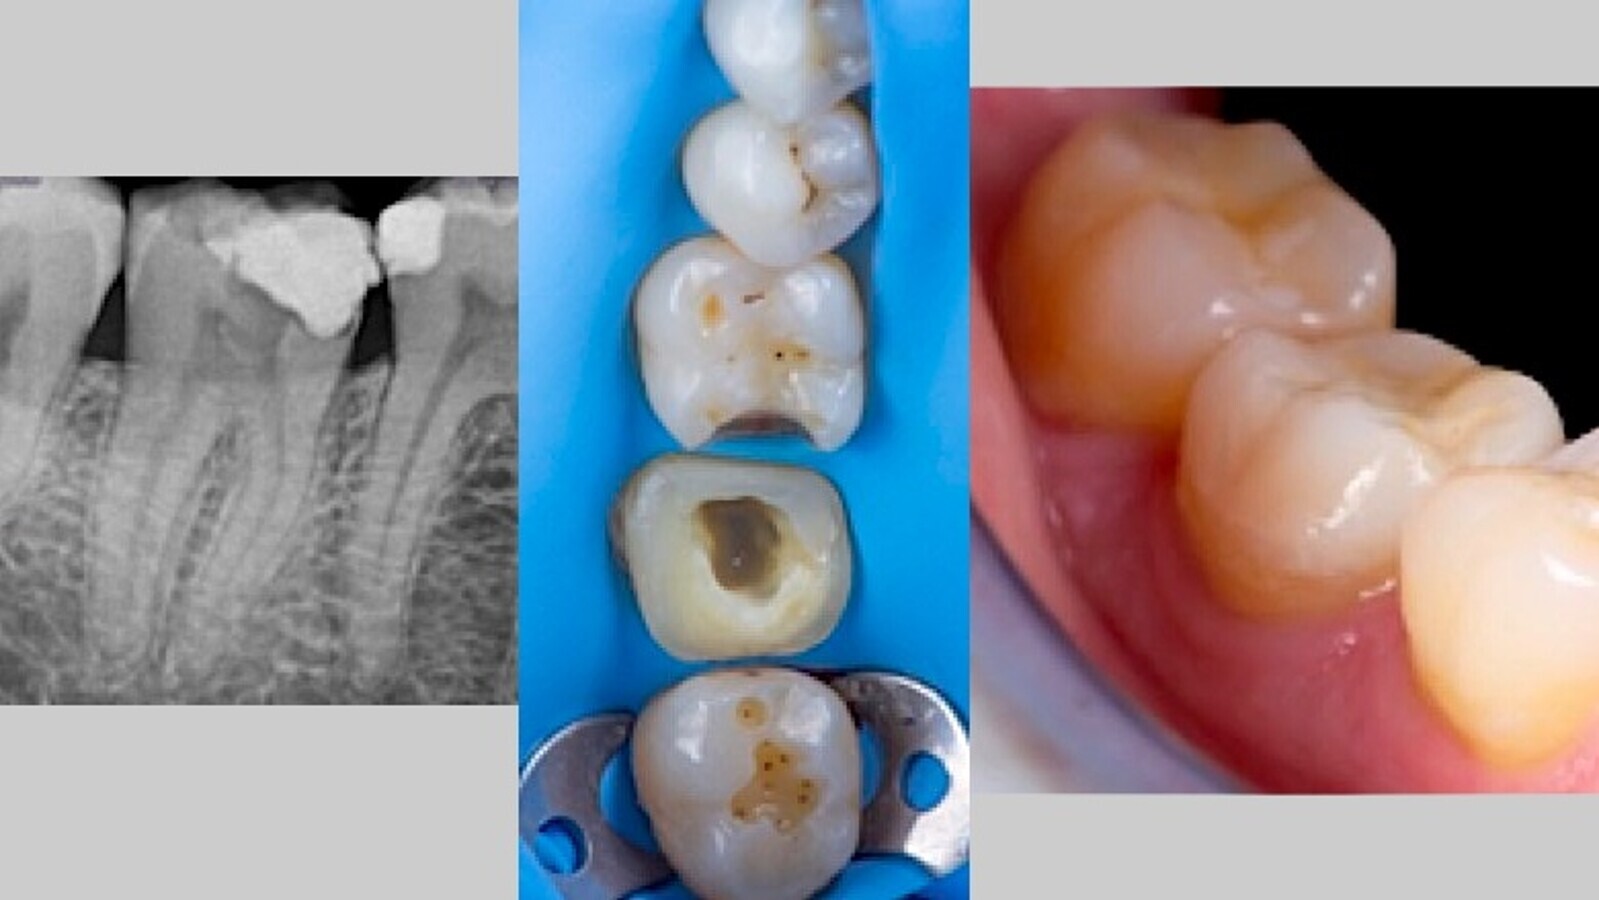

Manejo clínico de una pulpitis irreversible

Tratamiento de pulpitis irreversible con periodontitis apical sintomática en el segundo molar inferior derecho por un equipo del Máster de Endodoncia Online de UIC-Barcelona.